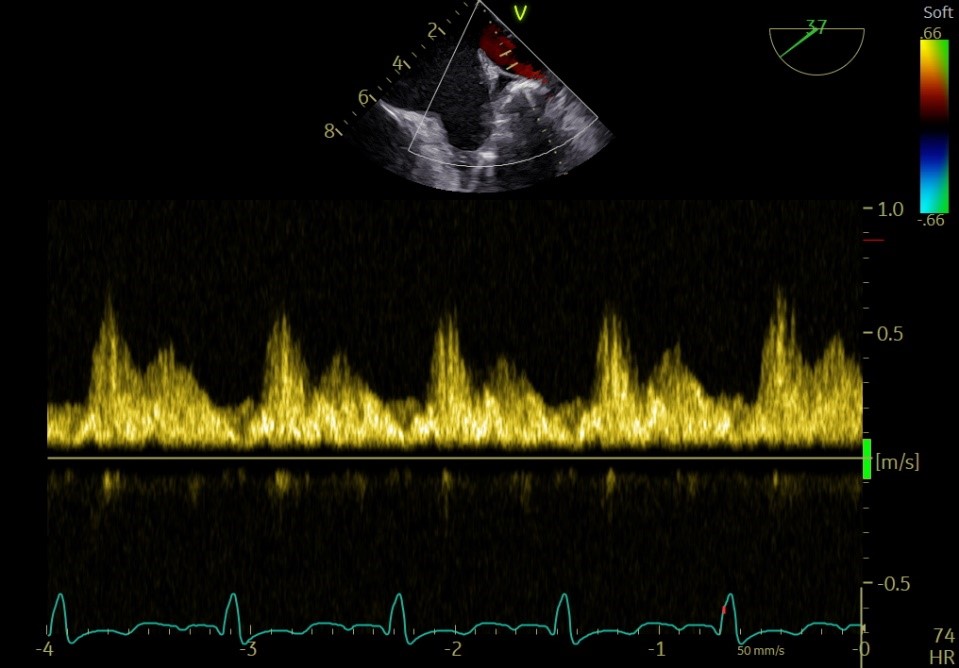

术前肺静脉频谱

释放后

术后肺静脉频谱